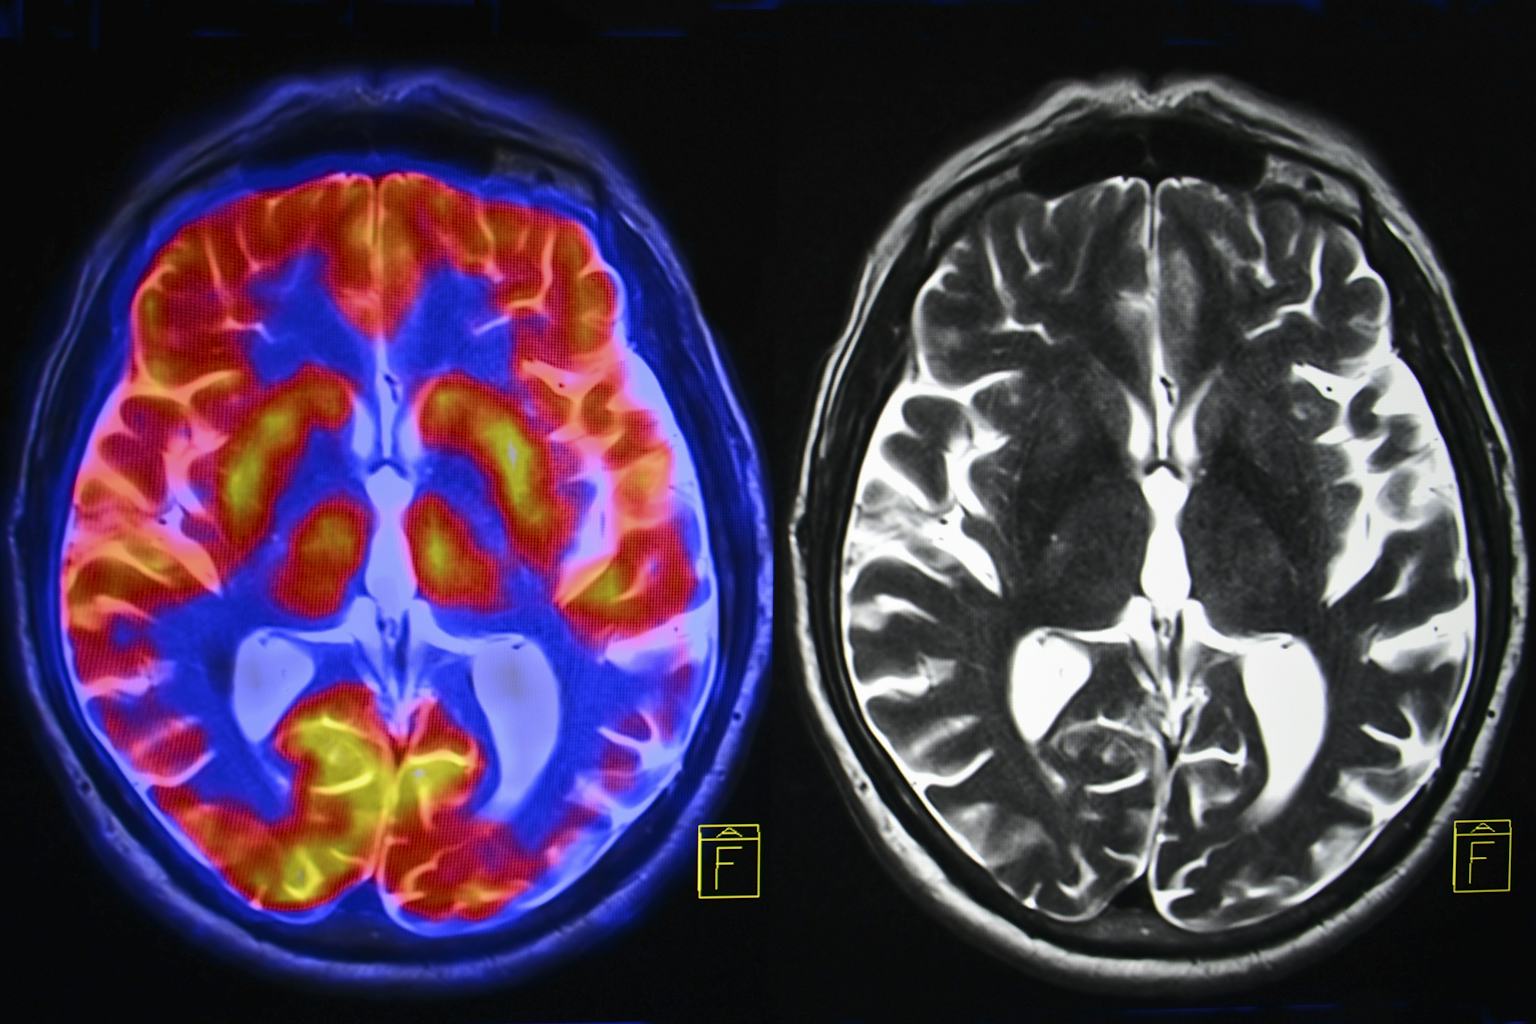

Acute stress is a sprint; chronic is a marathon that wears you down. When worries linger—work grind, money woes, endless scrolls—cortisol floods stay high, shrinking the hippocampus (memory hub) and amping the amygdala (fear center). Result? Foggy focus, emotional rollercoasters, and a 30% higher risk for anxiety or depression.

Science spotlights the damage: A UAB study found chronic stress accelerates brain aging, mimicking 10 extra years by eroding prefrontal cortex volume—your “wise owl” for decisions. Sleep suffers too: Elevated cortisol disrupts REM, leaving you irritable and accident-prone (hello, 40% more errors at work). My “aha” moment? During a high-stress job, I blanked on simple tasks—turns out, my hippocampus was playing hide-and-seek. Thought-provoking: If stress literally shrinks your brain, what’s one worry you’re ready to release today?